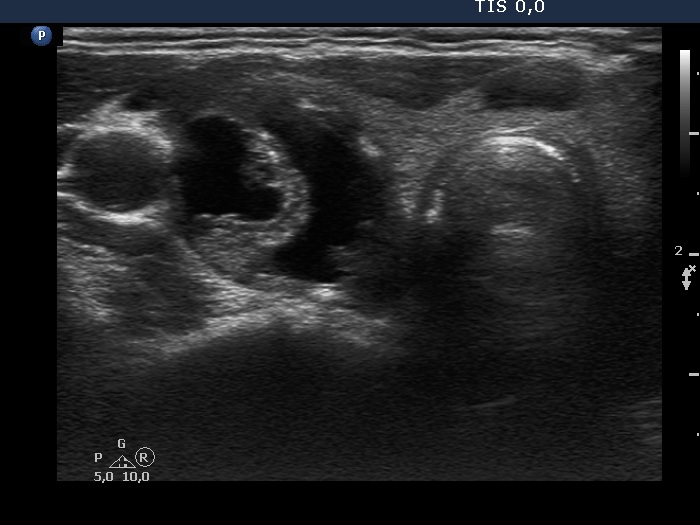

Benign cystic-colloid goiter (cytological diagnosis)

The hyperechogenic granules within the ventral solid part might be microcalcifications. The echogenic figures in the solid area cannot be the consequence of posterior enhancement because they are in front of the cystic area. Note that the nodule has in fact a moderately hypoechogenic solid part which seems to be echonormal dorsal to the cystic fluid because of the acoustic enhancement dorsal to the fluid.